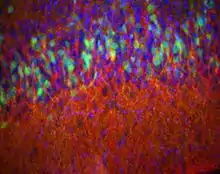

En anatomie des animaux, le paléocortex ou le paléopallium est une région du télencéphale du cerveau des vertébrés[1]. Ce type de tissu cortical se compose de trois lames corticales (couches de péricaryons)[2]. En comparaison, le néocortex a six couches et l'archicortex a trois ou quatre couches[3]. Étant donné que le nombre de lames qui composent un type de tissu cortical semble être directement proportionnel à la fois aux capacités que possède ce tissu à traiter l'information et à son âge phylogénétique, le paléocortex est considéré comme un intermédiaire entre l'archicortex (appelé également l'archipallium) et le néocortex (appelé également le néopallium)[1],[4].

Le paléocortex et l'archicortex du cortex cérébral constituent ensemble l'allocortex des mammifères ou le cortex hétérogénétique. Sa distinction avec ce qu'on appelle le néocortex, qui constitue la majeure partie du cerveau humain (environ 90 %), est faite à partir du nombre de couches cellulaires que comprend la structure. Le tissu néocortical comprend six couches cellulaires distinctes, que l'on ne voit dans les tissus paléocorticaux ni au stade adulte ni en développement.

Le paléocortex est présent dans le gyrus parahippocampique[1], le bulbe olfactif, le bulbe olfactif accessoire, le tubercule olfactif, le cortex piriforme, l'aire périamygdalienne[4], le noyau olfactif antérieur, l'espace perforé antérieur, et l'aire prépyriforme.